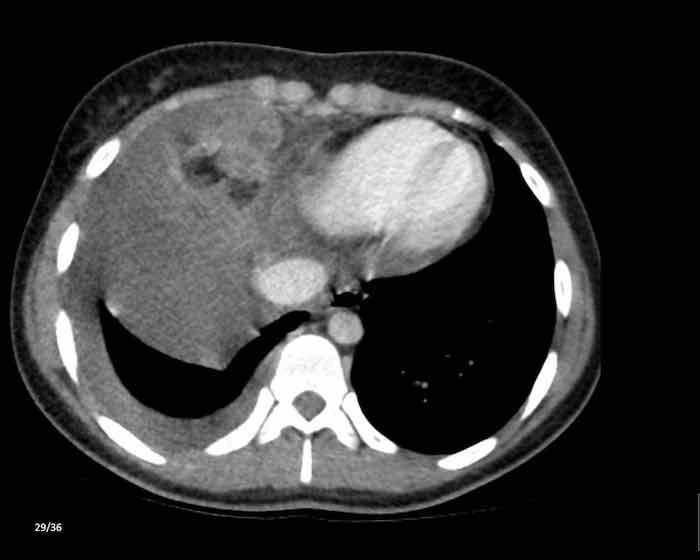

Các hình ảnh này của một nam giới 71 tuổi.

Trên CT ngực, tình cờ phát hiện một khối ở tuyến ức.

Hãy phân tích các hình ảnh. Nhận định của bạn là gì?

Hình ảnh

Một phần tổn thương có ngấm thuốc cản quang và có một số vôi hóa, có thể nằm ở thành nang.

Khi một tổn thương tuyến ức có thành phần đặc, nguyên tắc là… “khi còn nghi ngờ, hãy phẫu thuật cắt bỏ”.

Tổn thương đã được phẫu thuật cắt bỏ dựa trên kết quả CT và kết quả giải phẫu bệnh cho thấy đây là u tuyến ức dạng nang.